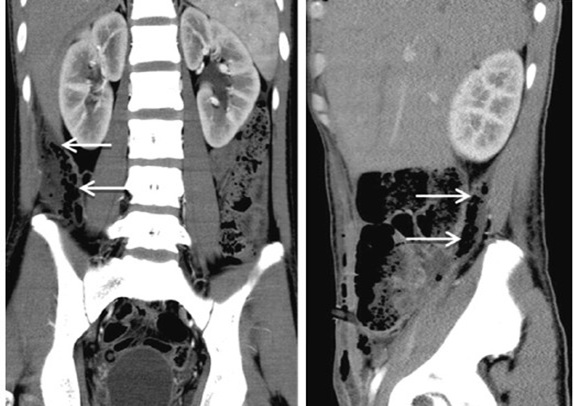

Các mũi tên trắng chỉ hình ảnh khí ở khoang sau phúc mạc bên phải

Đứng trước những bệnh nhân có biểu hiện triệu chứng của một áp xe khoang sau phúc mạc, chúng ta cần phải khai thác kỹ những dấu hiệu sớm có thể định hướng tới nguyên nhân là do viêm ruột thừa sau manh tràng vỡ và rò ra khoang sau phúc mạc, như: đau mơ hồ vùng hố chậu phải và phía trên mào chậu, rối loạn tiêu hóa, sốt … Qua đó để đưa ra quyết định chụp CTscan ổ bụng sớm là hết sức cần thiết. Hình ảnh đặc trưng của viêm ruột thừa sau manh tràng vỡ và rò ra khoang sau phúc mạc giai đoạn sớm là hình ảnh khí ở khoang sau phúc mạc (Retroperitoneal Air) phía sau manh tràng. Với giai đoạn muộn chúng ta vẫn thấy những hình ảnh khí sau phúc mạc, tuy nhiên lúc này hình ảnh khí có thể lan tới đùi, bìu dái, sau dưới gan, hoặc thậm chí lên tận màng phổi và trung thất